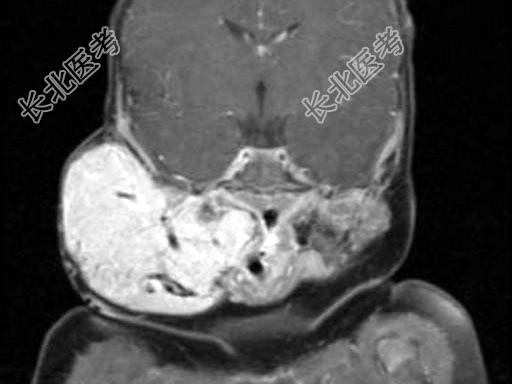

- 单项选择题老年患者,右侧面部肿胀, 呈青紫色,MRI检查如图所示, 最可能的诊断是 ( )